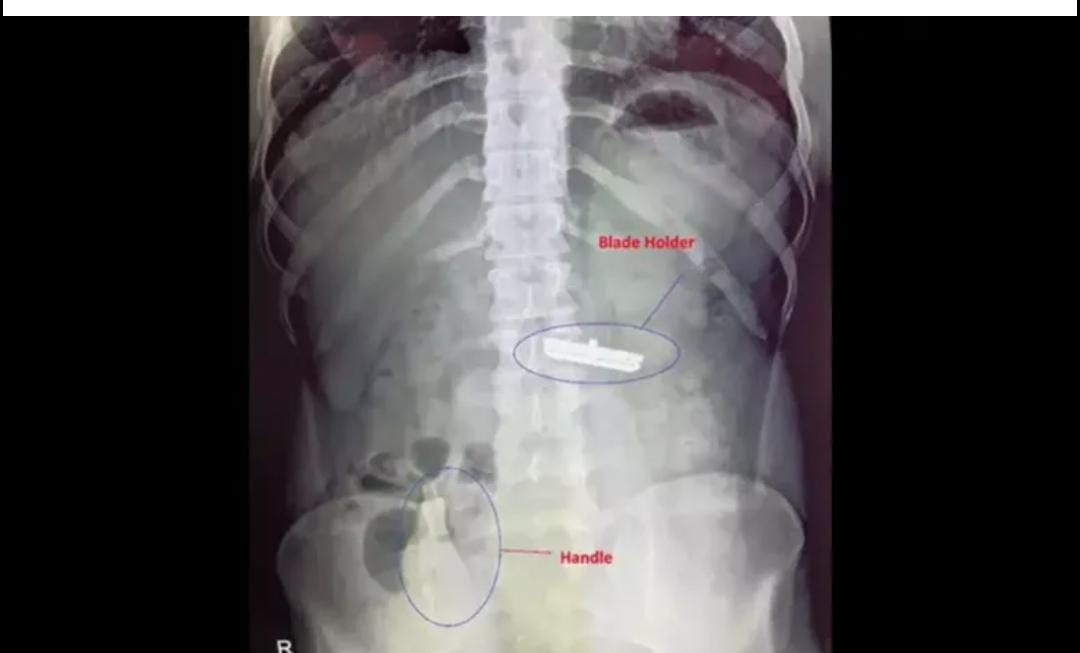

ഉടനെ ആശുപത്രിയിലെത്തിച്ച യുവാവിന് ഡോക്ടർമാർ വിദഗ്ധ ചികിത്സ നൽകി. സ്കാനിംഗിന് വിധേയമാക്കിയപ്പോഴാണ് ബ്ലേഡും ഹാൻഡിലും വയറ്റിലുണ്ടെന്ന് വ്യക്തമായത്. ബ്ലേഡ് ഇയാളുടെ ആമാശയത്തിൽ തങ്ങിനിൽക്കുന്ന അവസ്ഥയിലായിരുന്നു. എന്നാൽ ഹാൻഡിൽ വൻകുടലുവരെയെത്തി.

ഉടനെ ഇയാളെ ശസ്ത്രക്രിയയ്ക്ക് വിധേയമാക്കിയതോടെ യുവാവ് രക്ഷപ്പെടുകയായിരുന്നു. അടിയന്തര ശസ്ത്രക്രിയക്കൊടുവിൽ ഷേവിങ് സെറ്റ് യുവാവിന്റെ വയറ്റിൽ നിന്നും പുറത്തെടുത്തത്.